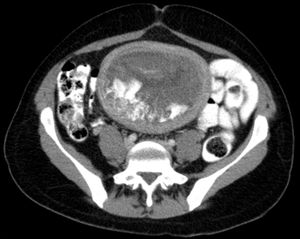

초음파 사진에서 기태는 포도송이("포도송이 떼", "벌집 자궁", "눈보라")와 유사하게 나타난다.[14] CT 촬영을 통해 자궁강 내에 과립상의 구조가 관찰된다.